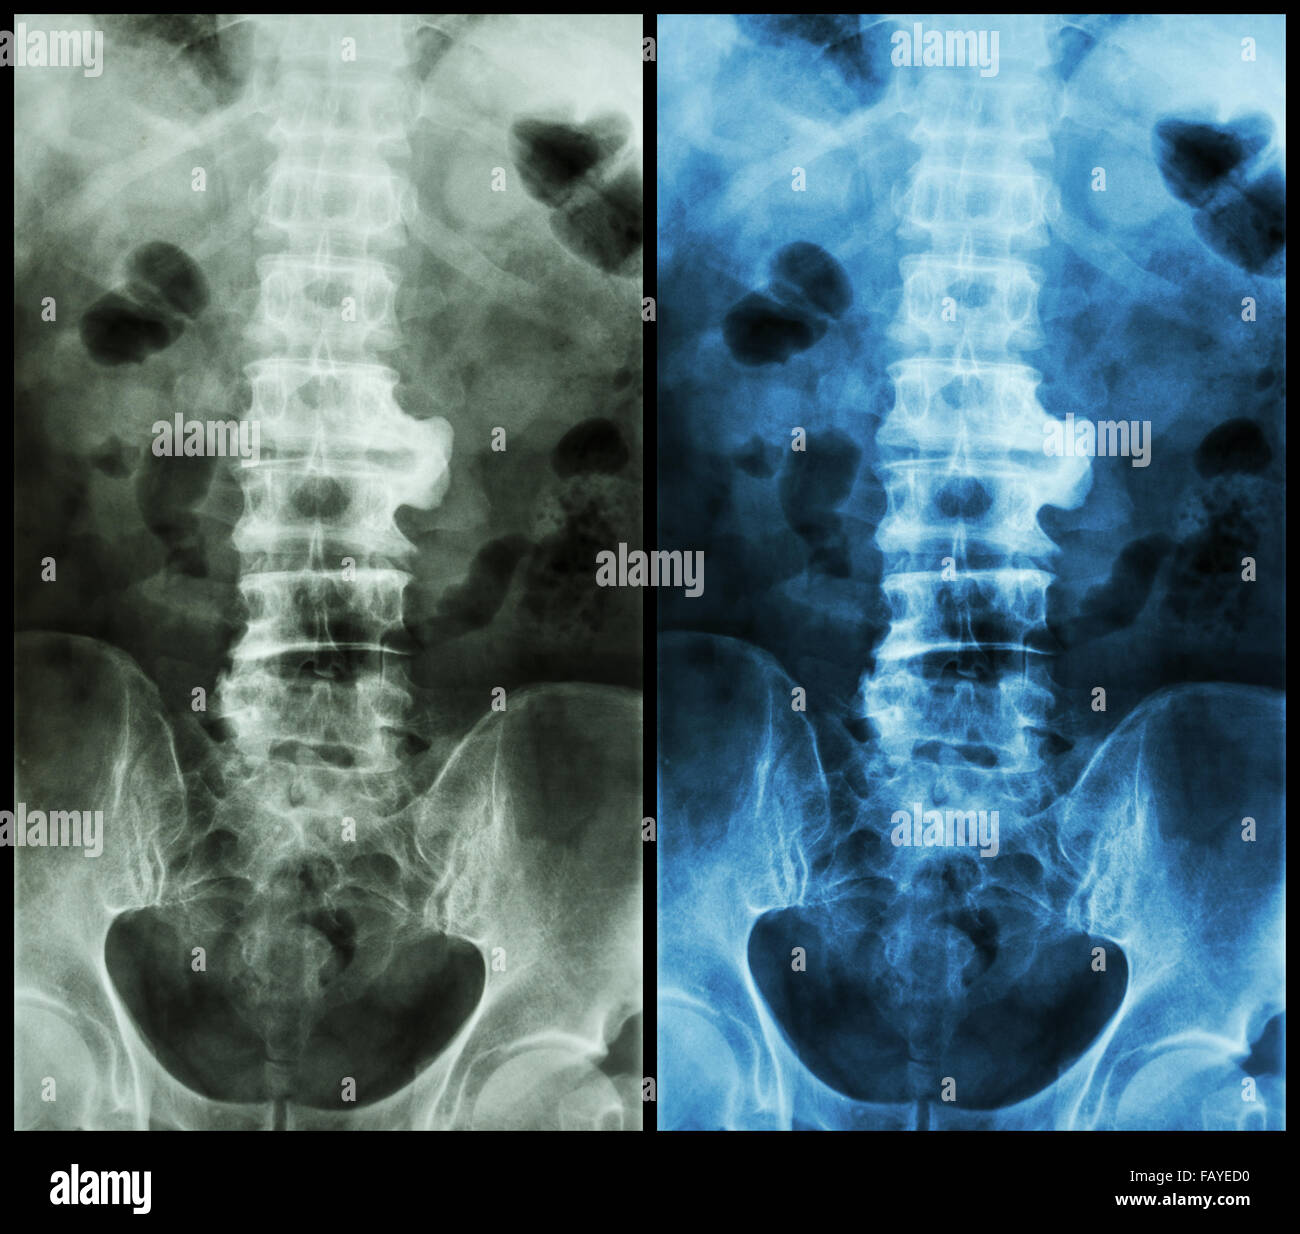

Plain X-ray of the thoracolumbar spine taken in anteroposterior view …

Scoliosis film x-ray lumbar spine AP : show spine bend in old aged …

Xray Image Of Adult Patient Spine Show Scoliosis Surgery Fix By Long …

Spondylosis And Scoliosis ( Film X-ray Lumbar – Sacrum Spine Show …

X-ray, anteroposterior view of the lumbosacral spine sh | Open-i

X-ray Of Lumbosacral Spine, Frontal Sagital View Scoliosis Royalty-Free …

Normal Human S Lumbosacral Spine Stock Photo – Image of care, patient …

Spondylosis and Scoliosis ( Film X-ray Lumbar – Sacrum Spine Show …

Xray Lumbar Spine Show Degenerative Change Of Disc And Body Of Spine …

X-ray image lumbar spine stock image. Image of disc, medical – 95002091

Spondylosis and Scoliosis ( film x-ray lumbar – sacrum spine show …

Pin on X-rays

Spondylosis and Scoliosis ( Film X-ray Lumbar – Sacrum Spine Show …

Spondylosis ( film x-ray lumbo – sacral spine : show spondylosis at L2 …

X-ray image lumbar spine stock image. Image of column – 95002161

Scoliosis Film X-ray Show Spinal Bend In Teenager Stock Photo – Image …